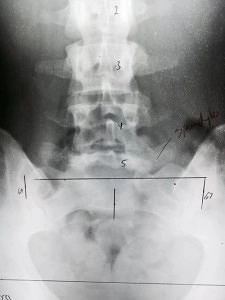

A spondylolisthesis ("Spondylo" or "Spondy" for short) is the anterior movement of a vertebral body. The word itself is derived from Greek: spondylos = vertebra, listhesis = slippage. There are 5 types of spondylolisthesis:

Spondylolisthesis in Grand Rapids MI overall occurs most commonly at L5 (90%) but degenerative type is most commonly at L4. Very rare incidence also occurs in the cervical spine (neck). The severity of a spondylo is determined by a grading system determined by the amount of slippage that has occurred but the amount of slippage is not directly related the the amount of symptoms experienced.

- Grade I = 0-24%

- Grade II = 25-49%

- Grade III = 50-74%

- Grade IV = 75-99%

- Grade V = 100%